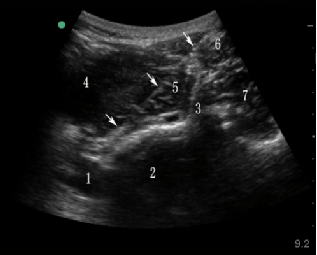

超声引导后入路腹腔神经丛阻滞超声图像

1.腹主动脉 2.腰2椎体 3.横突 4.肾脏

5.腰大肌 6.腰方肌 7.竖脊肌 箭头:穿刺针